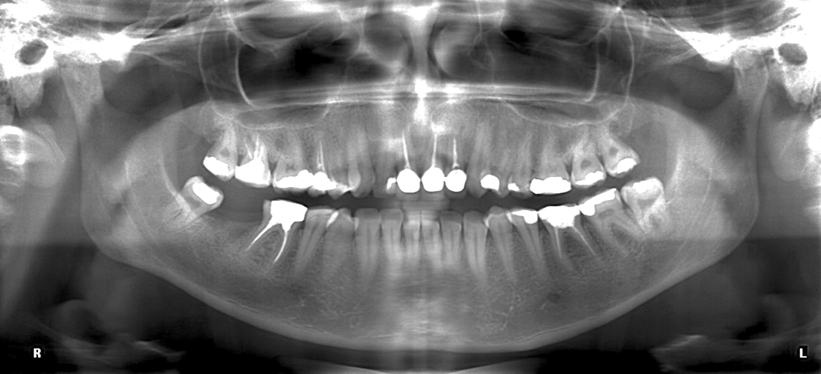

下顎管(図1)は下顎体部に位置し、オトガイ(3)まで伸びています。下顎管と下顎歯の根の関係は様々です。親密な関係から全く接触がない関係まで、さまざまな関係があります(4)。

図1: 下顎管

図 2: 下顎管が歯 38 番と 48 番の下にあることを示すパノラマ X 線。